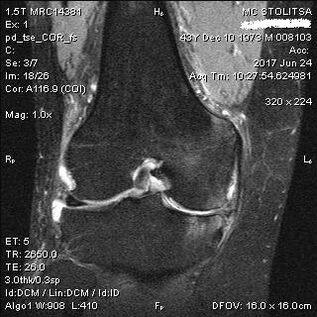

Ṣiṣayẹwo aisan arthrosis ti apapọ orokun waye ni ọfiisi ti ẹrọ ipakokoro rheumtology tabi Orthopedist. Dokita ṣe ayẹwo apapọ apapọ, palages o, tẹtisi awọn ẹdun ati beere awọn ibeere afikun. Ṣiṣe awọn idanwo pupọ - fun apẹẹrẹ, béèrè alaisan lati tẹ ẹsẹ rẹ tabi rin igbesẹ diẹ. Lẹhinna, ti o ba jẹ dandan lati salaye ipele ti arun tabi iseda ti awọn ayipada eegun, oun yoo tọka si ọ fun awọn ijinlẹ afikun. Fun apẹẹrẹ, fun isunmọ-demograping tabi aworan iwoyi.